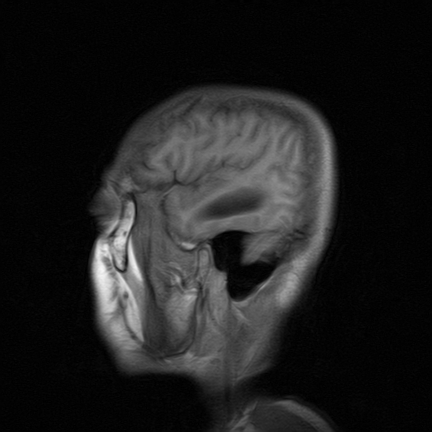

标题: MRI2064:少见病例。男性52,视力下降多年。 [打印本页]

标题: MRI2064:少见病例。男性52,视力下降多年。

四脑室区见混杂信号占位影,脑室系统扩张明显,临近结构显著受压称位,患者52岁,多考虑室管膜瘤可能性大

考虑第四脑室室管膜瘤并阻塞性脑积水。

应该是来源于小脑蚓部的占位,如血管母细瘤或星形细胞瘤

小脑蚓部胶质脑膜瘤突入四脑室;肿瘤内见血管流空信号和钙化信号.

比较典型的脉络丛乳头状瘤并脑积水,鉴别小脑蚓部血管母细胞瘤。